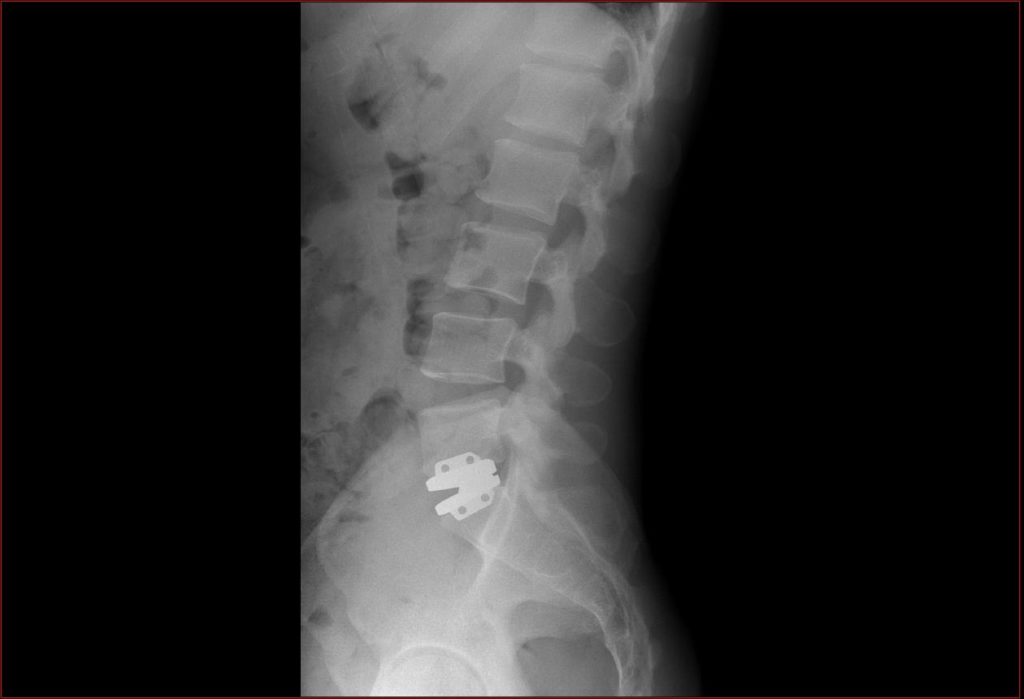

Source: mytraderkra.pages.dev PPT SCM Imagerie Médicale Cagnes sur Mer / Vence Centre Monégasque de Télé Radiologie , Dans certains cas, l'infiltration lombaire L5-S1 peut ne pas être recommandée ou souhaitée par le patient. Une infiltration lombaire L5-S1 concerne l'articulation entre la dernière vertèbre lombaire (L5) et le sacrum (S1)

Source: empleaklt.pages.dev Discopathie L5 S1 définitions, causes, symptomes LesMauxDeDos , Hernie discale postéro-latérale gauche à l'étage L5-S1,avec compression radiculaire probable Il est important de noter que l'infiltration lombaire L5-S1 n'est pas un traitement curatif, mais plutôt un moyen de soulager temporairement les symptômes de la douleur lombaire

L5 s1 hires stock photography and images Alamy . Infiltration lombaire l5-s1 avis; L5-s1 - Accueil - Rhumatologie ; Discopathie protrusive l5-s1 - Accueil - Mal de dos ; À cet étage, cela concerne les sciatiques (pour les cruralgies, plus rares, l'infiltration se fait plus haut).